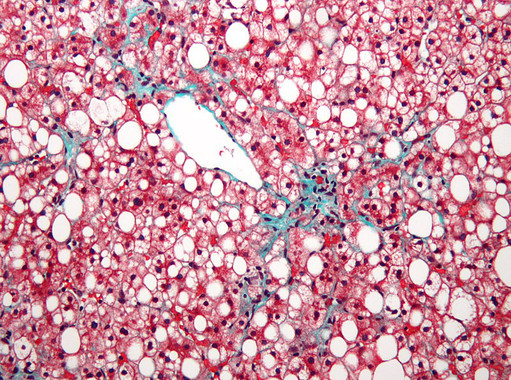

Nuevos determinantes implicados en el desarrollo de hígado graso no alcohólico

Agencia SINC Un nuevo estudio realizado por Manuel Vázquez Carrera, investigadora del CIBERDEM y la Universidad de Barcelona, ha permitido descubrir nuevos determinantes implicados en el desarrollo de la enfermedad del hígado graso no alcohólico, la alteración hepática más común y cuya incidencia ha alcanzado proporciones epidémicas en el mundo. Esta patología incluye un amplio abanico de […]